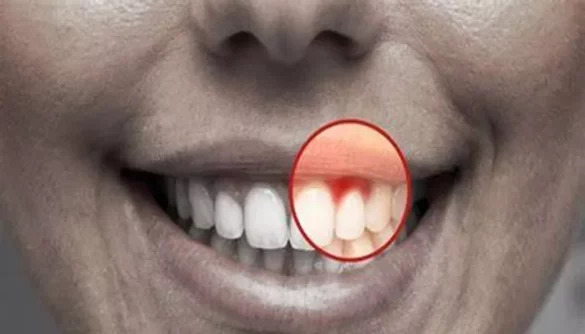

Dentures are a popular solution for individuals who have lost their natural teeth. Whether you’re new to dentures or have been wearing them for a while, sore gums are a common issue. While dentures can restore your smile and improve your quality of life, they can sometimes cause discomfort, irritation, or pain in your gums.

Before we dive into solutions, it’s important to understand why sore gums develop when wearing dentures. Dentures are artificial replacements for missing teeth, but they rest on the soft tissues of your gums. Since dentures are not a perfect fit in the beginning, they can sometimes cause friction, pressure, and irritation. Over time, this friction can lead to sore, inflamed, or tender gums.